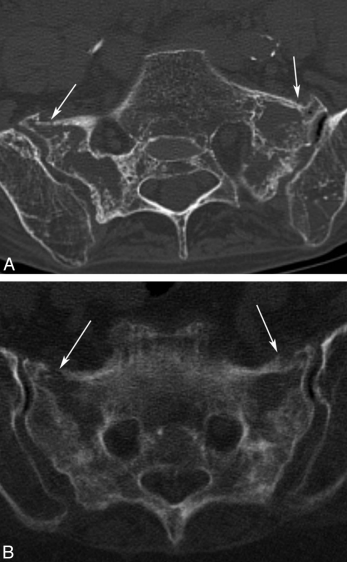

骶骨机能不全骨折 CT 表现

骨质疏松、骨质密度减低,骨皮质或骨小梁断裂,可见骨折线显示,骨折线位于骶孔外侧,平行于骶髂关节,多为双侧,也可为单侧,冠状位显示「H」征,骨折愈合期显示骨质硬化改变。

骶骨机能不全骨折 MRI 表现

早期骨髓水肿呈长 T1 长 T2 信号改变,显示细微骨折较 X 线、CT 敏感,当出现双侧骨折线冠状位可构成典型「H」征,增强扫描骨折线表现为线样低信号,周围骨髓水肿明显强化。